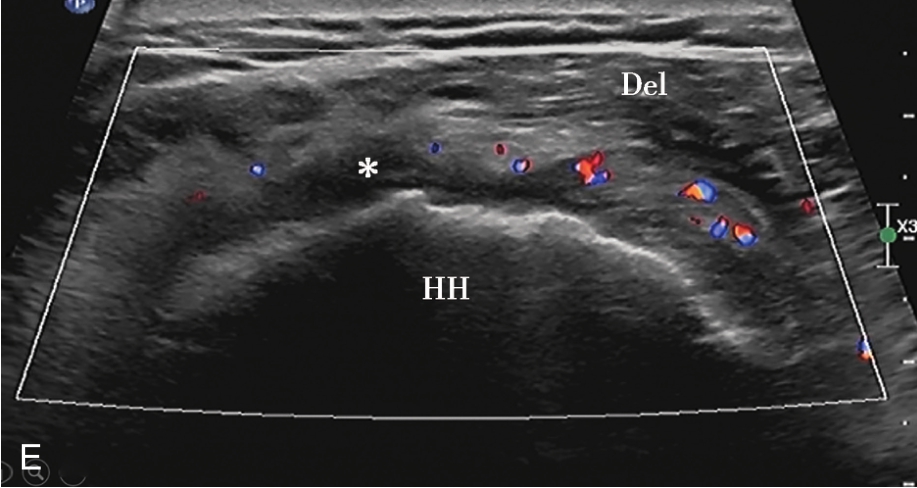

C.彩色多普勒显示囊性团块(星号)内无血流信号;D.超声造影显示囊性团块内呈无增强;E.冈上肌腱完全断裂,关节腔积血(星号);F.超声引导下穿刺液体抽吸及药物注射治疗,箭头示穿刺针